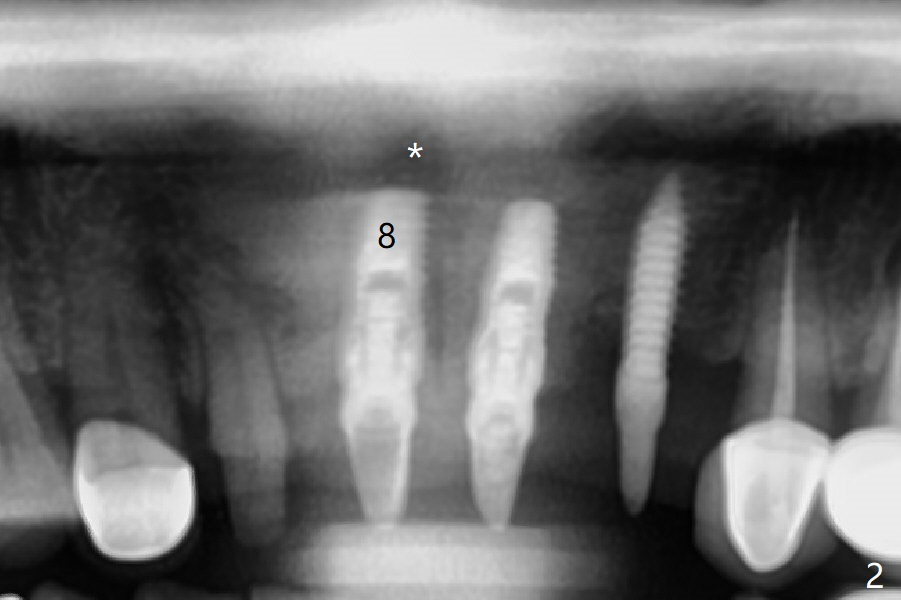

A 45-year-old woman returns for #7-10, 22/23 and 25 restoration; the implant at #10 appears to be inflamed (Fig.1 *). With free hand placement, the implant at #8 seems to be close to the Incisive Canal (Fig.2,3 *), while those at #9, and 10 are buccally placed (Fig.4,5 B). The implant at #10 will be replaced with a smaller one palatally (Fig.6 green). In fact the patient requests #9 implant redo because of protrusive crown.